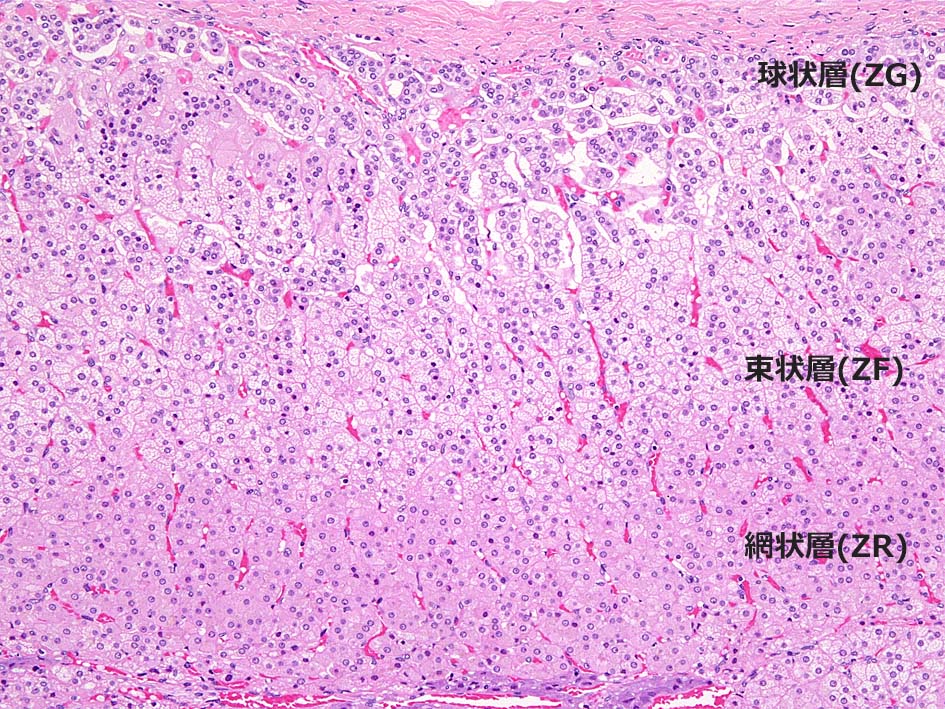

皮質には境界の不明瞭な3層構造が認められる. 被膜直下より, 球状層(Zona Glomerulosa), 束状層(Zona Fasciculata), 網状層(Zona Reticularis)と呼ばれ各々性状, 形態の異なる細胞より構成されている.

球状層(ZG):

球状層細胞は境界明瞭な細胞で少量の線維血管性間質で囲繞された小型クラスターを形成している. クラスターはときに集簇して短い柱状, 直線状, 曲線状, あるいはヘアピン様の形状をしめすことがある.

淡い好酸性, amorphous(無構造)な細胞質でわずかに空胞状を呈する. 核は卵形で他の皮質層細胞と区別は困難であるが, より小型でクロマチンに濃染する.

束状層(ZF):

皮質の1/2を占め幅が最も広い層. ZG, ZRとの移行は形態的に不明瞭. 束状層細胞は大型で, 円形核と豊富な細胞質をもつ. 細胞2個分の幅を有する長い柱状構造を示す.

核は球状層細胞に比べよりvesicularで, クロマチンは淡い. 外側2/3細胞の細胞質は脂肪を豊富に含むため泡沫状, スポンジ様の淡明な所見を示す.

網状層(ZR):

網状層は副腎尾側部では通常欠損している. 網状層細胞は皮質の1/4程度の厚さを占め, スポンジ様の網目構造を形成し周囲には拡張した血管が存在する.

網状層細胞は境界明瞭な細胞で, 束状層細胞より小型であり, 顆粒状, 好酸性の細胞質をもち, 脂肪含有量は少ない. 髄質近傍の網状細胞はリポフスチンを含むため黄褐色を呈する.